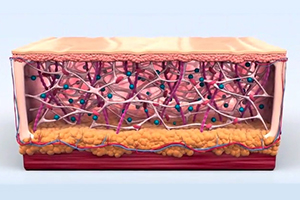

피부 표면과 평행한 3D 원통형 열기둥을 생성합니다. 최적의 피부 자극을 위해 6~70도의 열 온도를 5초간 진피층에 노출시킵니다.

-

Step 3.

시술 후 조직 검사 결과 진피 중간층의 콜라겐이 증가, 진피 탄력섬유(elastic fiber)가 탄탄하게 재정렬된 것을 확인됩니다.